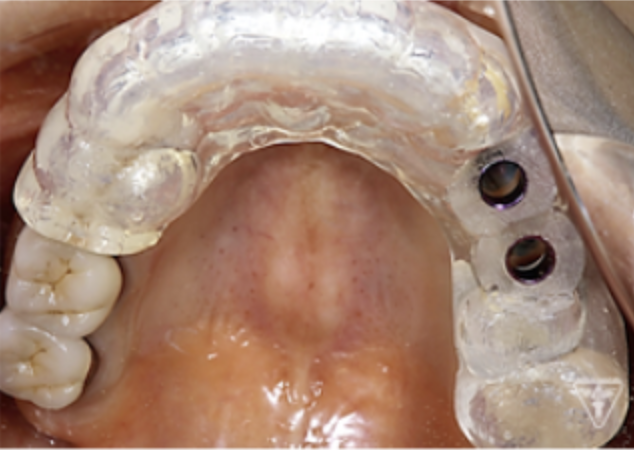

サージカルガイドの作成